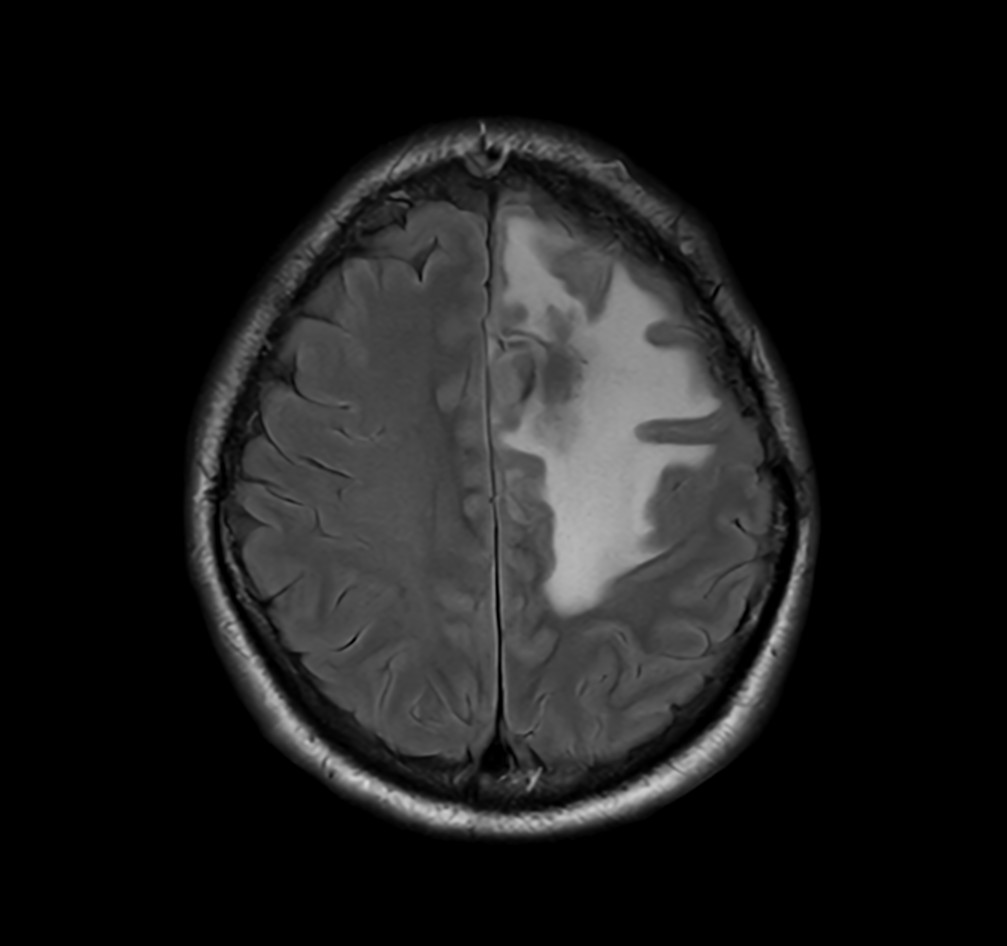

SmartSpeed Precise imaging for brain with glioblastoma